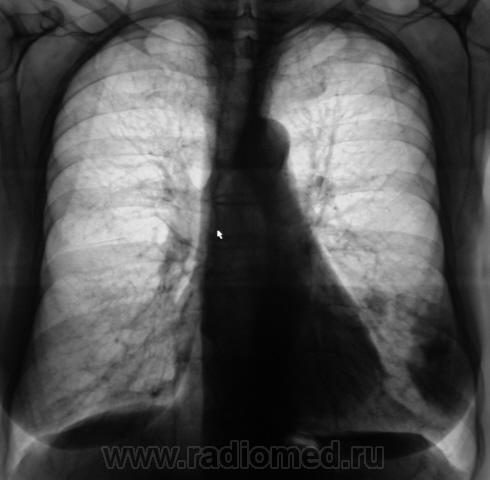

Контроль после флюорографии. Стандартное дообследование.

Ваше мнение уважаемые коллеги?

Mts? Но откуда? Что в анамнезе?